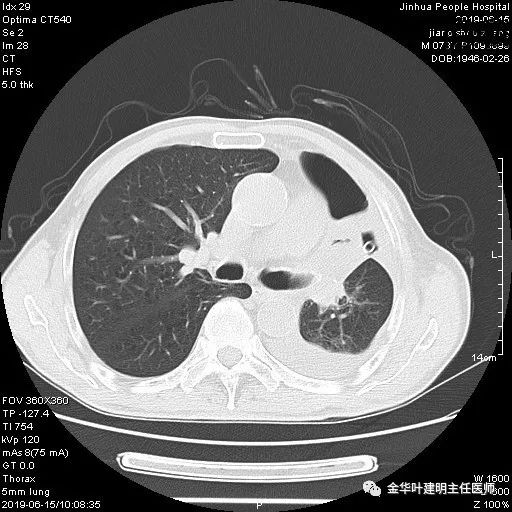

患者,男性,73岁,金华人。因“咳嗽咳痰伴胸闷2月,检查确诊左肺癌1周”入院。气管镜: 气管支气管内较多脓性分泌物,左肺上叶前段管腔新生物,局部活检、毛刷。气管镜病理:(左肺活检)鳞癌。阅胸部CT见左上叶开口处新生物,考虑需左上叶袖式切除及淋巴结清扫。具体CT表现如下:

6.15上午:24小时胸管引流出血性液250ml;复查胸部CT示: